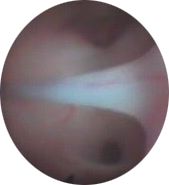

Vista endoscópica del fresado del

conducto óptico. |